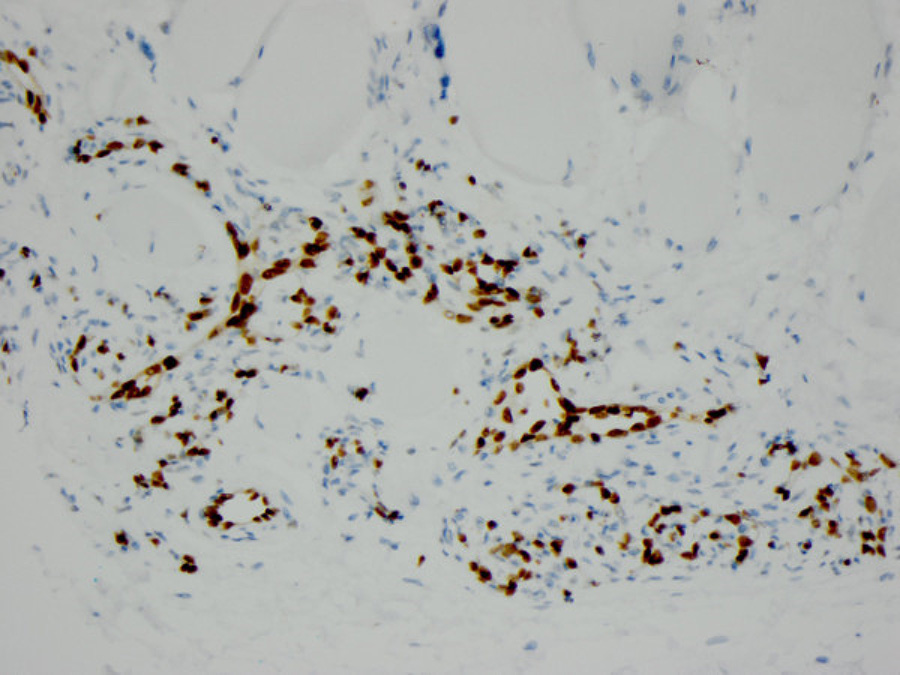

Histologically, the biopsy demonstrated numerous benign, variably-sized vascular spaces infiltrating the skeletal muscle (Figure 2). Mature adipose tissue was also present within the lesion (Figures 3). An immunohistochemical stain for ERG was performed and highlighted the vascular spaces within the lesion (Figure 4). The patient subsequently underwent radical resection of the tumor which had the same morphology as the core needle biopsy with numerous small benign vessels and mature adipose tissue within skeletal muscle (Figure 5).